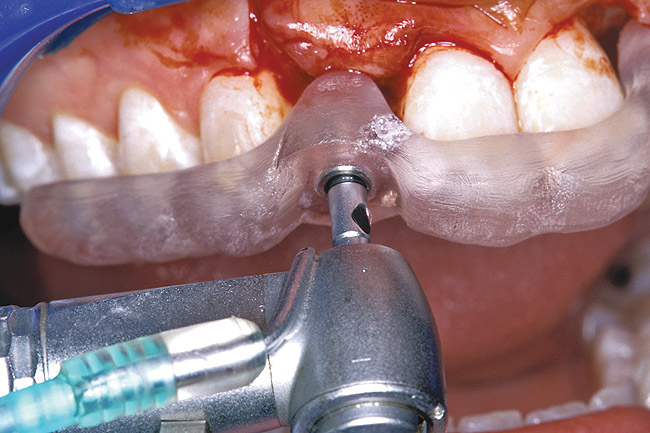

Before the day of surgery, the patient was seen by the orthodontist for the removal of the orthodontic brackets. The patient still was not pleased with the position of the two centrals, and it was determined that this would be addressed after implant placement (Figure 26). The anatomical variations of the crestal tissue and lack of interdental papilla can be appreciated in the close-up views of the right and left sites (Figure 27 and Figure 28). There were no surprises on the day of surgery as all of the decisions were made during the planning phase, before the scalpel ever touched the patient. The occlusal view of the CT 3D model revealed the wider alveolar ridge on the right side and thinner crest on the left side (Figure 29). This was confirmed when the full-thickness mucoperiosteal flaps were elevated, and the underlying bone revealed (Figure 30). The tooth-borne templates were designed to facilitate the drills and drilling sequence specific to the diameters of the predetermined implants (Figure 31). Each template contained an embedded 5-mm long stainless steel tube, which was approximately 0.2-mm wider than each drill (just wide enough to allow for the drills to rotate freely). Once positioned over the natural teeth, the template was secure and offered precision accuracy in transferring the implant locations from the original software-designed plan, allowing the potential for internal and external irrigation (Figure 32).

Figure 32  VIRTUAL PLANNING AND SURGERY A surgical template was derived from the final treatment plan created in the software, which facilitated the drilling sequence and precise location of placement.

Figure 32